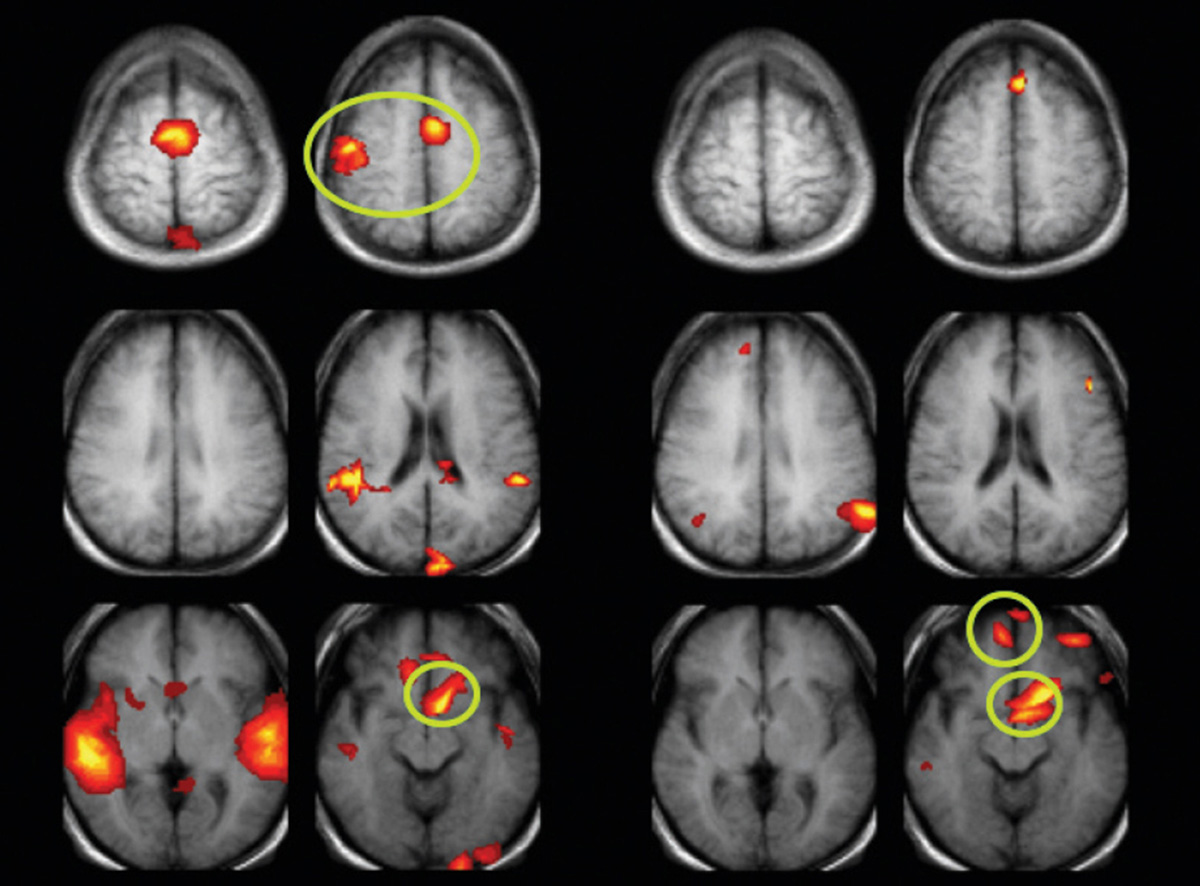

Если провести сканирование мозга смеющегося человека и сравнить скан со снимками мозга спокойного человека, можно увидеть, что у первого более активна лимбическая система. Это довольно древнее скопление структур, которое контролирует функции многих органов, отвечает за поддержание внутренней среды организма, за обоняние, за память, а также участвует в формировании поведенческих реакций и эмоций.

Снимки мозга слева сделаны в то время, пока испытуемый беззвучно смеялся под аудиозаписи смеха других людей. Снимки справа — в том время, пока человек читал сборник анекдотов. Зоны активности мозга почти не совпадают.

В исследовании смеха от щекотки, опубликованном в журнале Cerebral Cortex за июнь 2013 года, учёные разделили участников эксперимента на три группы. Людей из первой группы щекотали голые ступни, при этом разрешив вслух смеяться. Людей из второй группы ступни тоже щекотали, но велели подавлять смех. Людей из третьей группы вообще не щекотали, но попросили смех имитировать.

На время эксперимента каждого помещали в аппарат МРТ. Сканы мозга участников из первой группы выделялись на фоне остальных. В некоторых зонах активность была заметнее:

• в латеральной области гипоталамуса — она вовлечена в разнообразные процессы, например, в формирование пищевого поведения, подавление боли, контроль над пищеварением и артериальным давлением;

• в мозжечке — отвечает за зрительное внимание, язык и эмпатию;

• в миндалевидном теле — участвует в процессах формирования памяти, в принятии решений и отвечает за эмоциональные реакции.

Кроме того, в первой и третьей группе учёные зафиксировали активность в сером веществе среднего мозга, которое играет значительную роль в регуляции болевых ощущений.

Другое исследование Софи Скотт проводила с коллегами — его результаты опубликованы в журнале Neuropsychologia (январь 2017 года). Учёные сконцентрировались на двух категориях смеха: спонтанном и наигранном. Они предположили, что первый — искренний смех, которым мы смеёмся над забавными шутками, — часть более древней системы, а значит, он обрабатывается по-другому, нежели наигранный, вежливый смех.

Учёные собрали массив с записями этих двух видов смеха, а потом дали их послушать людям, которых поместили в аппарат МРТ. Оказалось, что человек отлично распознаёт на слух вид смеха, при этом на разные виды мозг действительно реагирует по-разному. При проигрывании спонтанного смеха по-особому активировалась слуховая кора, а при проигрывании вежливого — области, связанные с мышлением и представлением состояния другого человека. Иными словами, распознав фальшивый смех, человек пытается выяснить его причину, даже если понимает, что всего лишь слушает запись и смех к нему, в общем-то, не относится.